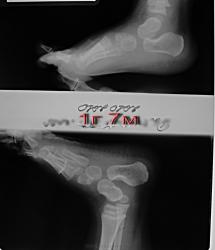

Направлен с диагнозом вертикальный таран.. Ваше мнение.

По-моему, надо расчертить оси таранной и пяточной костей и все будет видно. На вскидку - норма. Смущает угол в суставе Лисфранка.

Вертикального тарана однозначно нет. Когда он вертикальный, ось его практически отвесна. Встречается при врожденной плоской стопе. Цель исследования - исключение врожденного характера плоскостопия.

До 6 лет все дети плоскостопые в той или иной степени. Иногда возникает необходимость исключения врожденных аномалий стопы в более нежном возрасте для определения дальнейшей тактики лечения пациента. Подробнее не расскажу - не ортопед. А вообще по вопросу стоп рекомендую "Ортопедическую диагностику" Маркса.